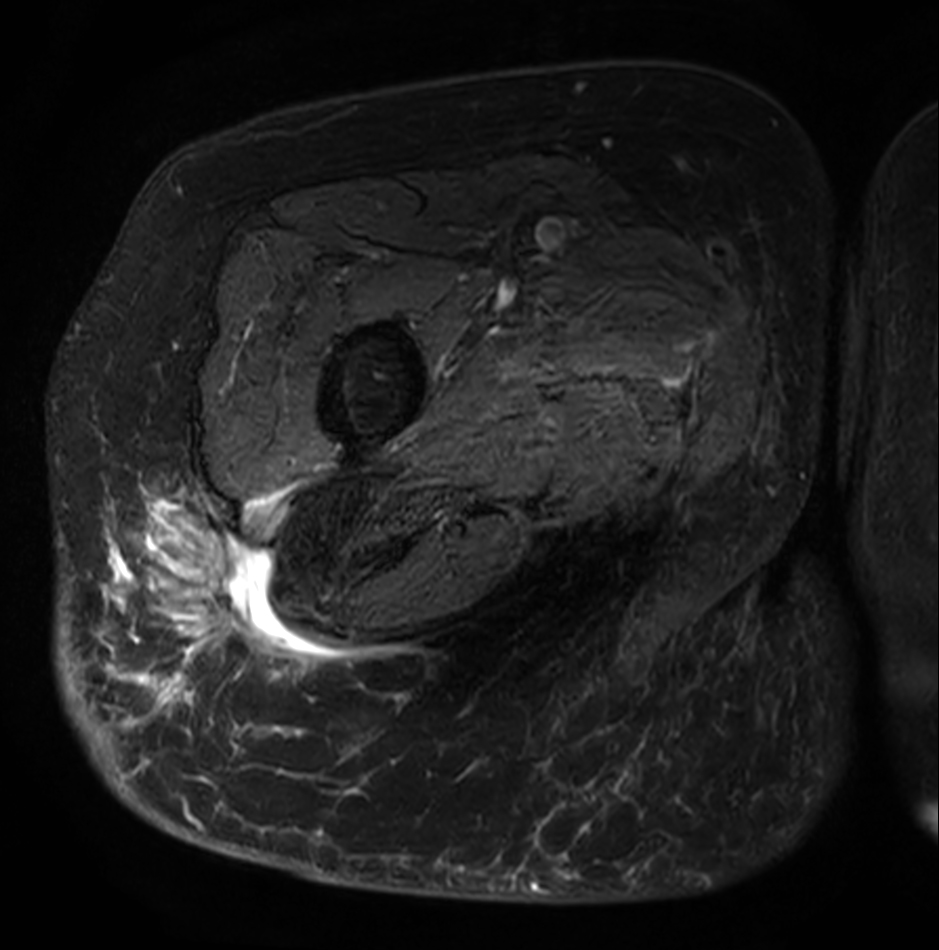

Axial T2w mDIXON XD TSE (Water only)

Axial T2w mDIXON XD TSE (In Phase)

Axial T1w SPIR +gado